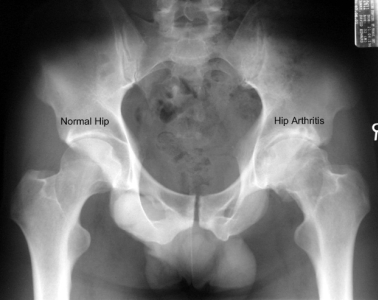

A simple x-ray should show changes of osteoarthritis. The x-ray findings classically include as joint space narrowing, subarticular sclerosis, osteophytes and degenerative cyst formation.